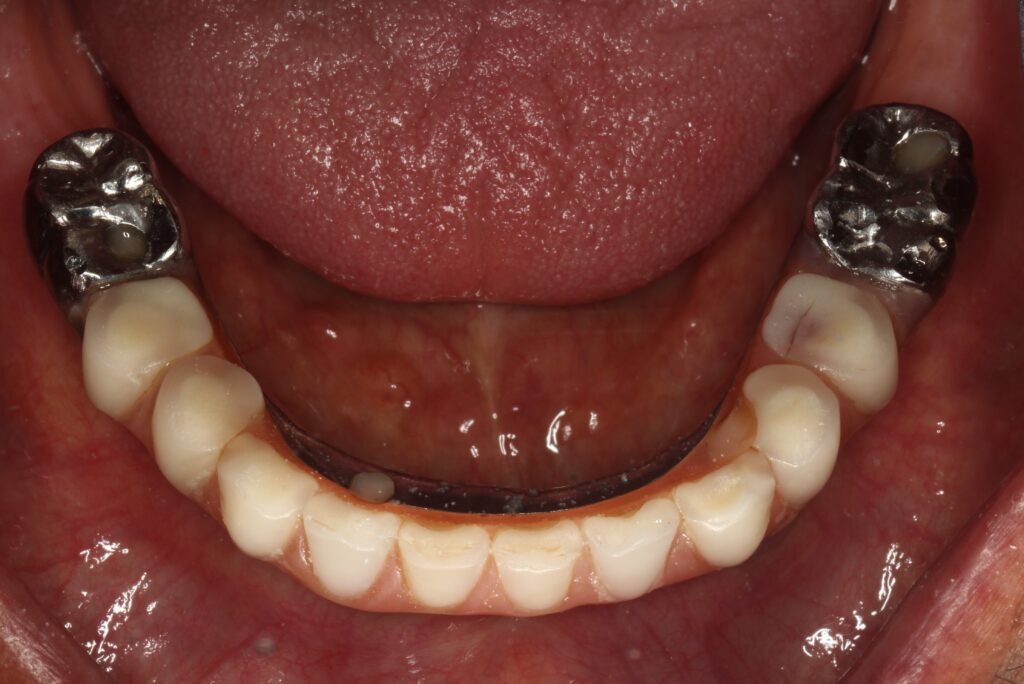

A selection of full arch fixed implant bridge patients after 5 years of wear